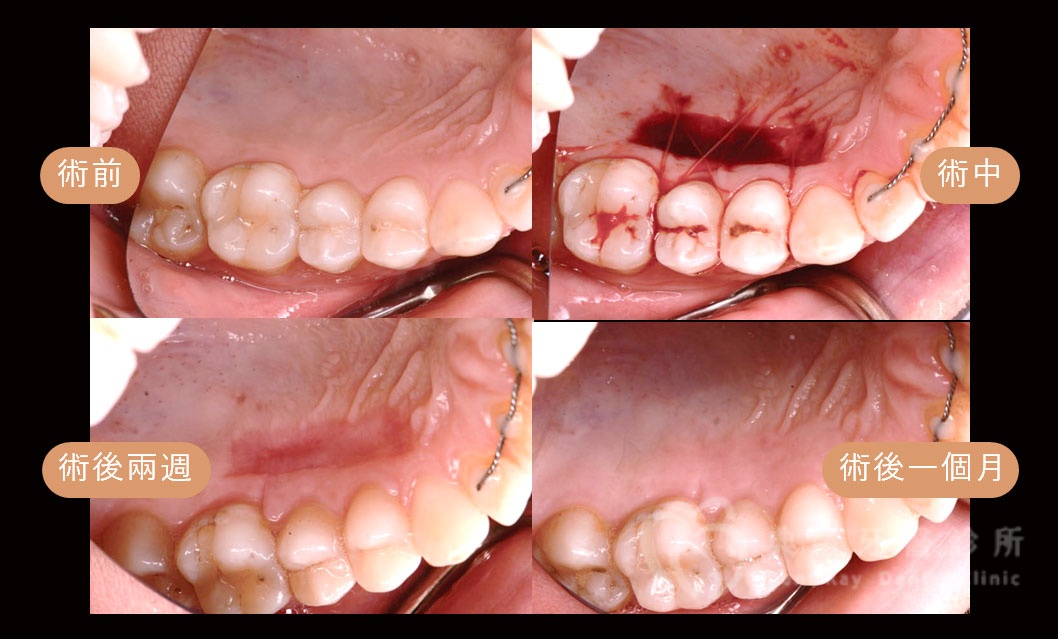

牙齦美學補肉手術